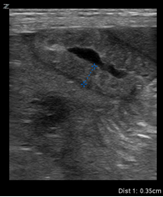

![]() |

| Thickened loop of small bowel (0.35 cm) | Thinning of colonic wall |